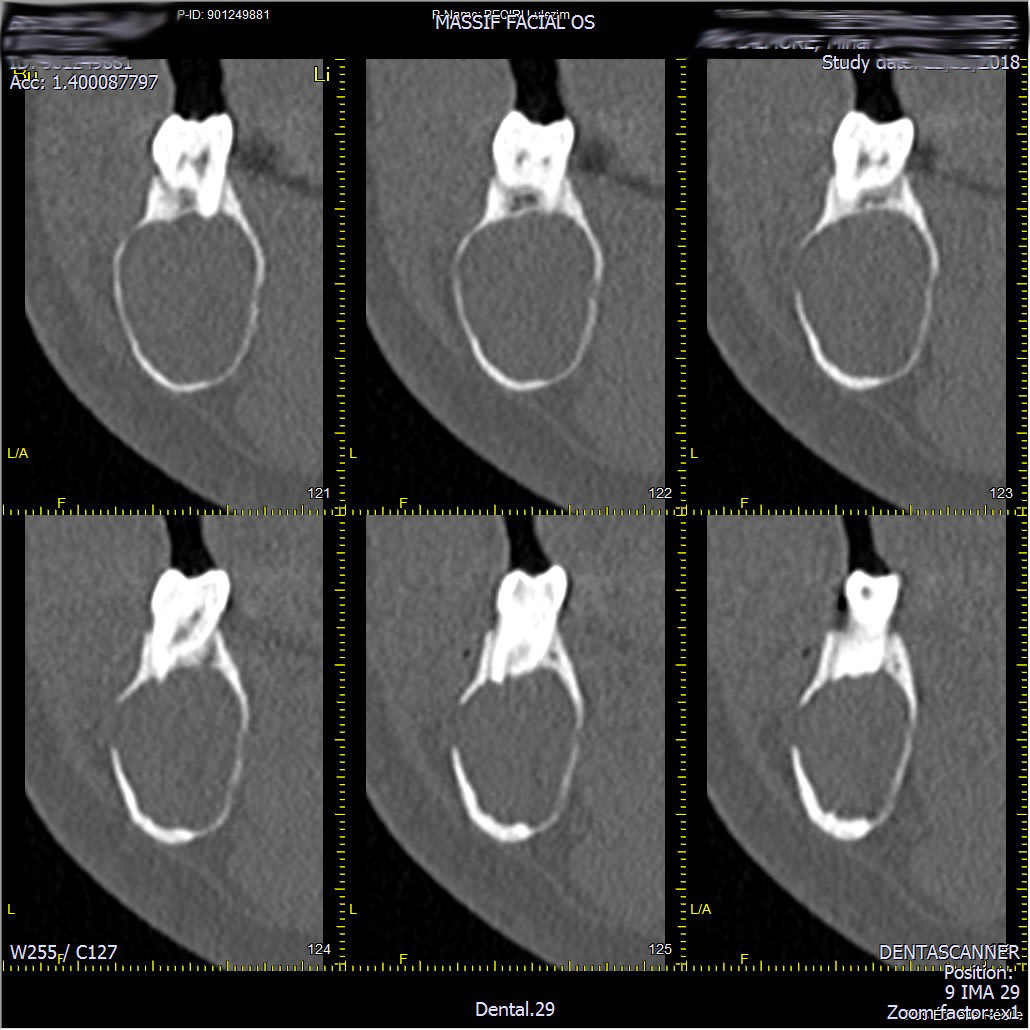

Voici les images du scan.

On se demande comment la mandibule tient...

Je vous ai mis une page sur 3.

Il va voir le chirurgien bientôt, je vous poste la suite dès que j'en sais plus.

La coupe transversale est tres impressionnante.